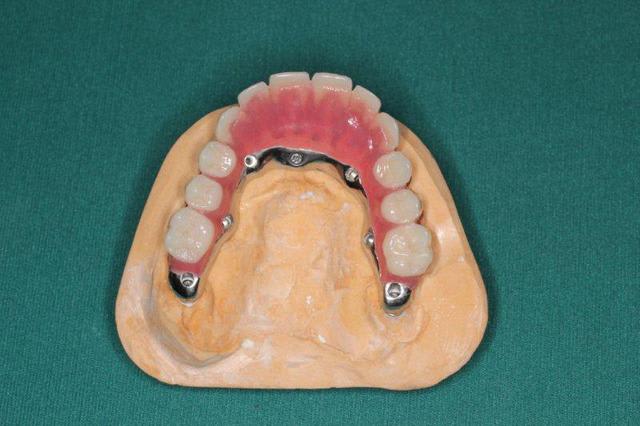

1. C est toi qui es malhabile... Rien de plus simple : tu mets ttes tes vis ds la puits, tu les recouvres d homéoplasmine pour les empêcher de tomber hors des puits, tu poses en bouche et tu passes ton tournevis ds homéoplasmine pour visser Très simple et très efficace :-))))

2. Effectivemeznt les plaques zygomatiques ont des émergences palatines mais au définitif j ai ôté les piliers prlongateurs de 3.5 mm et du coup même si sortie palatine plus aucun "débordement" du puits de vissage en dehors de l arcade...

3.Ca fait 18 mois que les implants sont en charge donc tu as déjà une idée mais de manière générale ça fonctionne aussi bien qu pilotis à la mandibule... Un petit coup de waterpik léger et qques bains de bouches suffisent à entretenir tout ça correctement

De tte façon si tu fais pas ce que je viens de faire, tu es cuit pour deux sinus-lifts ( dont la patiente ne voulait pas !!!!! )et encore tu n auras aucun implant au delà des 4 voire des 3 donc un terrible porte-à-faux devant... Sinon tu dois ajouter un Lefort pour interposer un bloc au niveau incisif... Elle refuse encore plus le Lefort que les sinus-lifts

Regarde le provisoire de la MCI : les émergences des plaques au niveau molaires font des bombés hors arcades suite à la pose de piliers monobloc de hauteur 3.5 mm

On pose ces piliers car il faut pouvoir retrouver facilement les têtes d implants 72 h plus tard pour poser la prothèse de transition

Pas le disk antérieur mais le disk et les 2 plaques antérieures pour être plus exact

La rougeur au fond du vestibule est due au frottement de la fausse gencive contre la partie libre muqueuse...

Au début elle ne frottait pas car j avais laissé un espace

Vouspourriez dire que je suis ds la merde car la difficulté d accès à l hygiène ds cette zone a provoqué cette inflammation qui serait préjudiciable aux implants...

Et bien je répondrais oui et non

OUI j ai eu les boules en voyant cette muqueuse gonfler au fil des mois car j ai cru que l inflammation alllait avoir raison de mes plaques...

NON pcq la prolifération de la muqueuse n est finalement pas due au manque d hygiène possible à cet endroit mais bien au fait d avoir utilisé un matériau de comblement effciace qui donne du vrai os et sur ce vrai os on retrouve de la gencive attachée, rose, ferme, soutenue et vascularisée...gencive qui prolifère au point de comprimer la fauuse gencive et la pas la fausse gencive qui comprime la muqueuse...

Mais si j avais fait la même chose avec de l INTERPORE , matériau corralien non résorbable, non seulement je n auaris pas obtenu de l os mais alors l inflammation aurait été réelle et aurait mis en péril mon implanto...

Pp